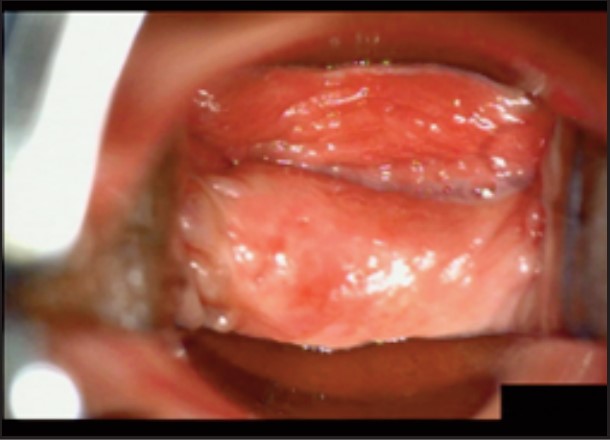

Під час спостереження до та після процедури, через 16 і 36 діб було зроблено вагінальні фотографії за допомогою Tele-Cervico (цервікографія) та виконано порівняння результатів до /після.

У пацієнток 1, 2 і 3 вагінальні складки утворилися та увиразнилися помітніше та сильніше, ніж вони були до лікування, ми оцінили цей клінічний результат після 1-го сеансу (через 16 діб). На нашу думку, такі виразні складки свідчать про підтяжку слизової оболонки піхви, що добре впливає на ущільнення піхви та проблему нетримання сечі. Через 36 діб після процедури ми спостерігали, що зруйнована анатомічна структура піхви відновила Н-подібну форму, тобто стала набагато здоровішою. Зокрема, у пацієнтки 4 структура піхви була цілковито зруйнована, стінки піхви обвисали через втрату еластичності. Однак через 36 днів після процедури структура піхви повністю відновила здорову Н-подібну форму [Див. Малюнок 3].

Пацієнтка №3

До

Після 16 діб

Після 36 діб

| Вік | 46 |

| Пологи | Природні. 2 хлопчики. |

| Лікування | 2 сеанси / 1 місяць |

| Огляд | 16, 36 діб |

| Протокол | 1 сеанс – 440 імпульсів 2 сеанс – 200 імпульсів |

| Результати | √ Відновлено H-подібну структуру √ Дещо зменшилися симптоми SUI √ Зросло задовлення партнера √ Зросло задоволення пацієнтки |